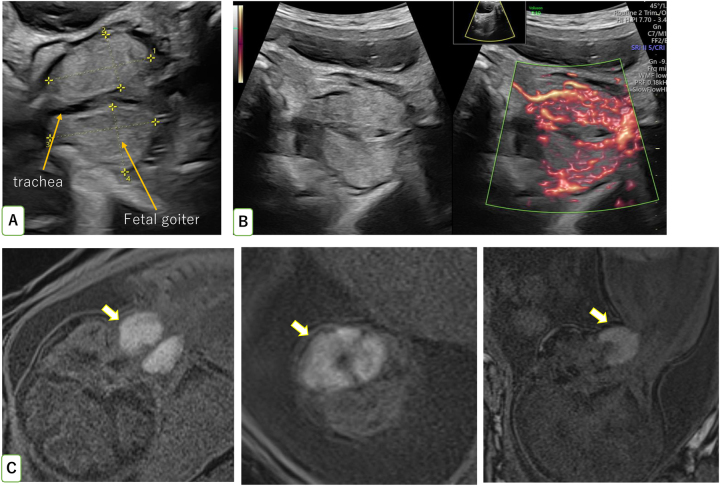

Case presentation: A 30-year-old pregnant woman with no history of thyroid disease was referred to our hospital with polyhydramnios. Fetal ultrasonography revealed fetal goiter. Cordocentesis revealed increased thyroid-stimulating hormone (TSH) and low levels of free thyroxine 4 (fT4), which was the basis of diagnosis of fetal hypothyroidism. Intra-amniotic injections of levothyroxine were administered, resulting in a reduction in the goiter size, amount of amniotic fluid, and level of maternal TSH. The mother was euthyroid during pregnancy. The infant was delivered vaginally at full term with a normal thyroid size and no respiratory disorders except hypothyroidism. At 2 years of age, her neurodevelopment is normal.

Conclusions: Intra-amniotic injections of levothyroxine for fetal hypothyroidism with massive goiter and polyhydramnios may improve perinatal outcomes.